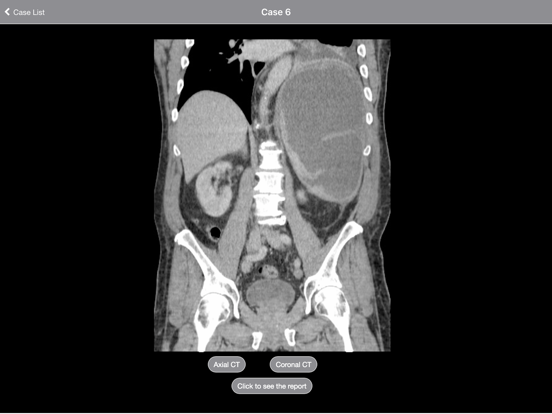

Each case is presented as a complete CT or MRI scan that you can scroll through as if at a PACS workstation. Multiple sequences in multiple planes are presented for every case. Report, short discussions, and pathology/clinical followup are presented for each case.

The interface incorporates image zoom and pan. In addition, both portrait and landscape orientations are supported.